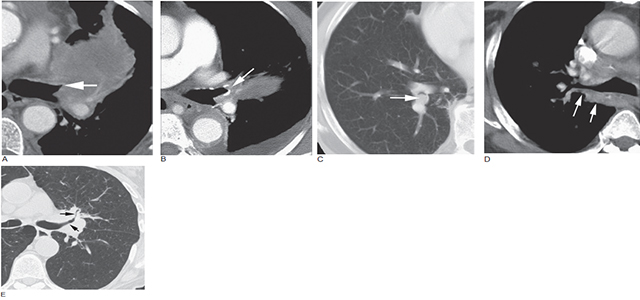

图6 肺癌的支气管异常

A. 左上叶支气管阻塞,显示锥形狭窄或鼠尾征(箭头),左上叶肺不张;B. 左肺上叶肺癌(箭头),相应支气管管腔截断;C. 右下叶支气管内可见息肉状的癌存在,周围为新月形气影;D. 右上叶支气管(箭头) 后壁增厚伴右肺门癌,常提示支气管浸润;E. 左肺门癌致左肺上叶和前段的支气管(箭头) 狭窄,可能由肿瘤浸润支气管壁或外部肿块压迫导致

图7 石棉暴露后的右肺门肿瘤

大的、边界不清的右肺门肿块包绕致右肺上叶支气管狭窄,为典型的小细胞肺癌的征象